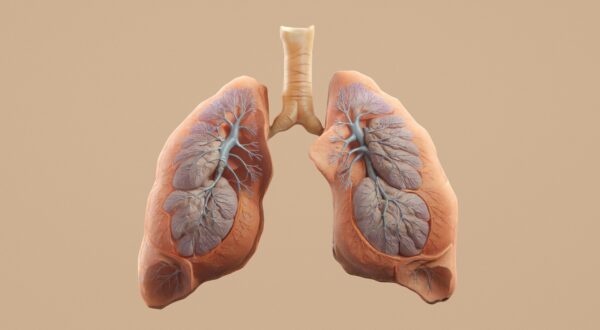

سرطان ریه یکی از مرگبارترین انواع سرطان در جهان است و سالانه میلیونها نفر را درگیر میکند. این بیماری معمولاً سالها در بدن رشد میکند بدون اینکه علائم مشخصی داشته باشد، و زمانی تشخیص داده میشود که درمان دشوارتر شده است. بنابراین، پیشگیری و تشخیص زودهنگام نقش حیاتی در کاهش مرگومیر ناشی از آن دارد. هرچند سیگار همچنان مهمترین عامل شناختهشده سرطان ریه است، اما پژوهشهای جدید نشان میدهد رژیم غذایی نیز میتواند نقش چشمگیری در افزایش یا کاهش خطر ابتلا داشته باشد.

این الگو برای هر دو نوع اصلی سرطان ریه، یعنی سرطان سلول غیرکوچک (Non-Small Cell) و سرطان سلول کوچک (Small Cell) نیز مشاهده شد.